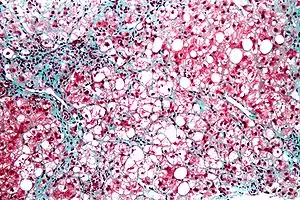

Micrograph of steatohepatitis. Liver biopsy using trichrome stain | |

Steatohepatitis is a type of fatty liver disease, characterized by inflammation of the liver with concurrent fat accumulation in liver. Mere deposition of fat in the liver is termed steatosis, and together these constitute fatty liver changes.[1]There are 2 main types of fatty liver disease (FLD):